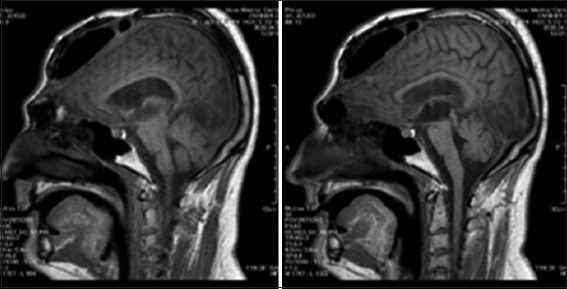

Case presentation: A 25-year-old male who had undergone bifrontal decompressive craniectomy suffered a severe traumatic brain injury. The autologous bone flap had been temporarily stored in a subcutaneous fat area of the abdomen for 3 months to preserve its viability. A secondary cranioplasty was then performed using titanium miniplates and self-tapping screws for final fixation. After 2 years, the patient developed empyema and a brain abscess; the infected bone flap was removed. A skull computed tomography (CT) scan was conducted, and a prosthesis was created from PMMA by employing CAD. In the sagittal plane, the defect extended from the frontal bone and surpassed the coronal suture, while in the coronal plane, it reached the temporal region on both sides. The prosthesis was fabricated through rapid prototyping based on CT scan images. Surgery was performed using a patient-specific prosthesis that adequately covered the defect area. Facial aesthetics were restored, and no complications occurred. The patient was followed clinically and radiologically for 1 year, during which no postoperative complications or signs of implant-related issues were observed.

Conclusion: This CAD/CAM single-piece PMMA implant successfully restored large bifrontal defects, suggesting that it may find broader applications in complex cranioplasties and could achieve improved outcomes.